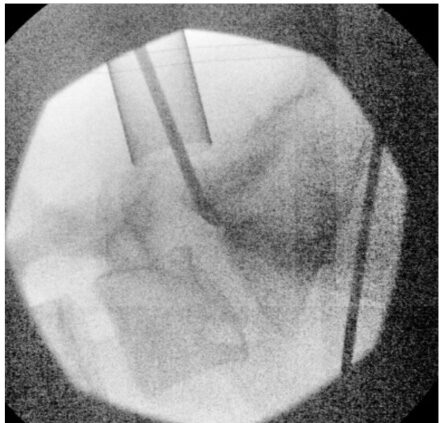

X-ray during surgery using MIS tubular retractor for microdiskectomy